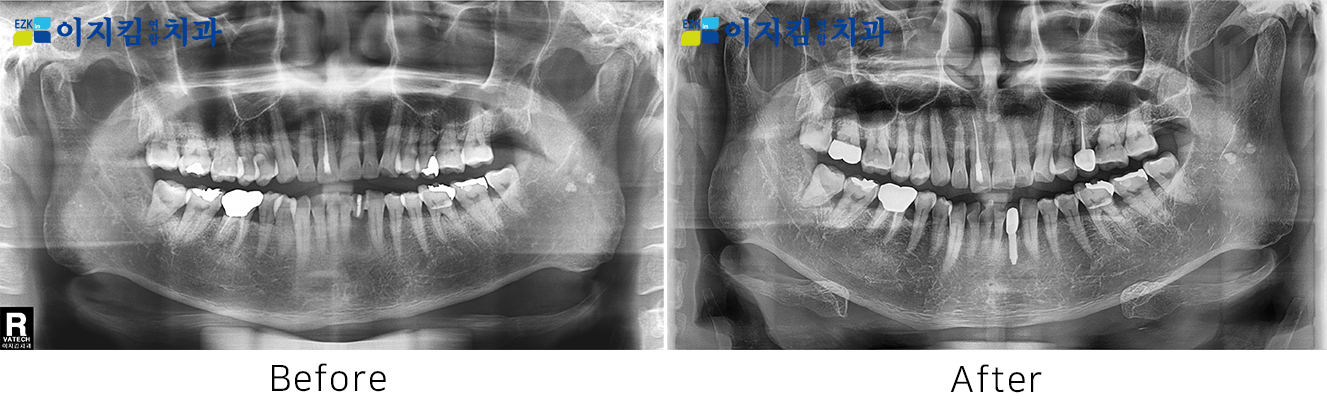

ÀÓÇöõÆ® Àü ¡¤ ÈÄ »çÁø

[

Á¶È¸¼ö : 3305

]